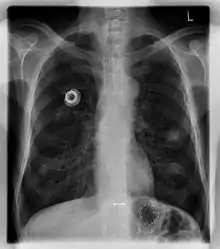

Chest X-ray showing an implanted port